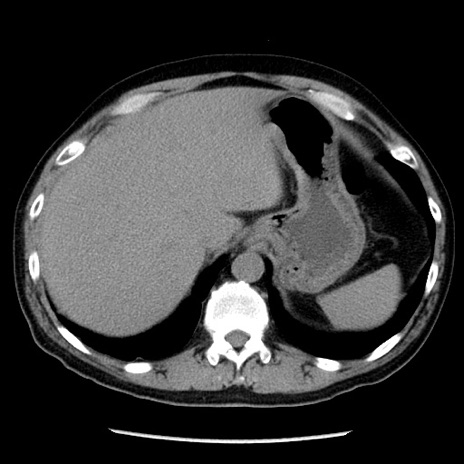

冠状断像

【症例】40歳代男性

【現病歴】2日前から胃痛あり。徐々に周期的な激痛に変化した。本日になっても激痛があるため受診。

【身体所見】意識清明、BT 38-39℃台あり、腹部:膨満、やや硬、右下腹部に圧痛あり。

【データ】WBC 8500、CRP 23.26